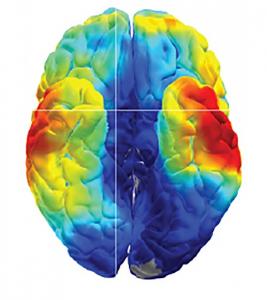

-les ondes cérébrales observées au moment de la mémorisation (enregistrement) et au moment du rappel (ici du second mot de la paire) se produisent majoritairement dans les zones du lobe temporal et du cortex préfrontal.

Dans la deuxième étude, les chercheurs ont utilisé un nouveau type de grille, un réseau de microélectrodes à haute densité, pour surveiller l'activité de dizaines de neurones individuels lors des tests de mémoire. Ces réseaux ont été implantés dans le gyrus temporel moyen, une zone du cerveau connue comme impliquée dans la reconnaissance des mots, des visages et de la distance. Cette seconde étude montre que les patients se souviennent correctement de 23% des paires de mots.

-le modèle de neurones activés lorsque les patients rappellent correctement une paire de mots semble être similaire au modèle de neurones activé lors de l'apprentissage ;

-ce modèle de neurones activés semble spécifique à chaque paire de mots individuelle apprise, et son activité est moindre lorsque le rappel semble plus facile pour le patient, suggérant que le cerveau n'utilise qu'une petite proportion de ces neurones pour rejouer alors le souvenir.

-Ces derniers résultats suggèrent que chaque souvenir est codé par un modèle unique de neurones individuels dans le cerveau.